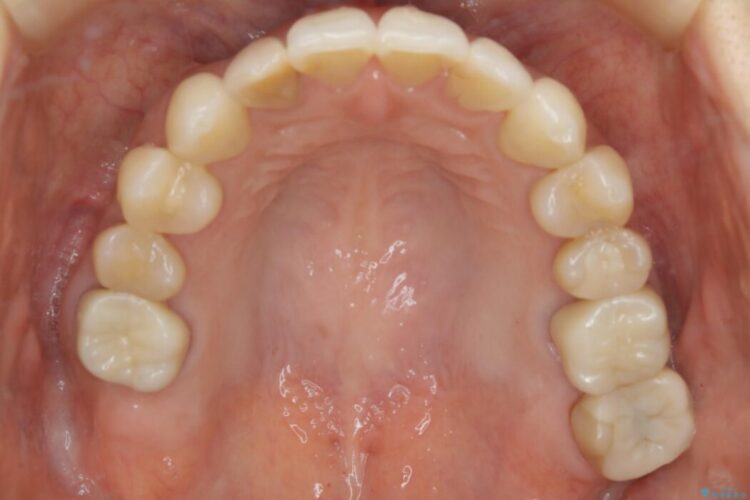

【30代女性】前歯の反対咬合をマウスピースで改善

全体的に歯列が狭窄しており、本来外側に覆いかぶさっている上の前歯が内側に入り込んでいました。

歯列弓全体の形状を整えるとともに歯の大きさもコントロールすることで非抜歯にて矯正を行いました。

気になっていたガタつきも改善され、患者様にはご満足いただけました。

歯列弓の拡大

歯並びが悪くなる原因の一つに「歯列弓の狭窄」というものがあります。

奥歯や前歯が内側(舌側)に倒れ込んでしまったり、歯が生えてくる位置が内側になってしまうことにより歯並びのアーチが狭くなってしまうことを言います。

このような場合、歯並びのアーチを拡大してあげるだけでもガタつきを無くすためのスペースがかなり作れることがあります。